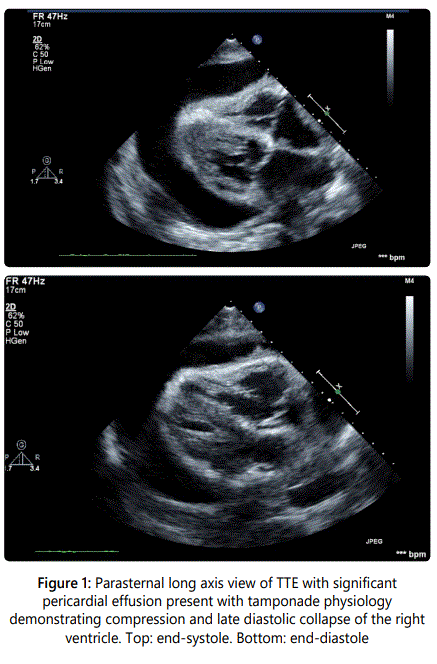

A 54-year-old gentleman with recently diagnosed Stage IIIB squamous cell carcinoma of the lung with metastases to the lymph nodes had a transthoracic echocardiograph (TTE) performed for evaluation of progressive dyspnea on exertion. A large pericardial effusion causing tamponade physiology was noted on TTE and the Computerized Tomography (CT) image of the thorax (Figures 1 and 2). Following a pericardi ocentesis, a repeat TTE was performed which showed the presence of a left atrial mass (Figure 3). The mass was initially reported as a 1.3x0.5 cm pedunculated mobile left atrial mass arising from the left atrial appendage prolapsing in the mitral orifice in diastole before further assessment with a transesophageal echocardiogram (TEE) was performed. The TEE demonstrateddirect invasion of the mass from the left upper pulmonary vein into the left atrial appendage with minimal residual flow of that pulmonary vein and complete opacification of the left atrial appendage as well as invasion of the superior vena cava (Figure 4). The mobile mass in the left atrium was a strand of tumor that extended from the edge of the left atrial appendage (Figures 5 and 6).